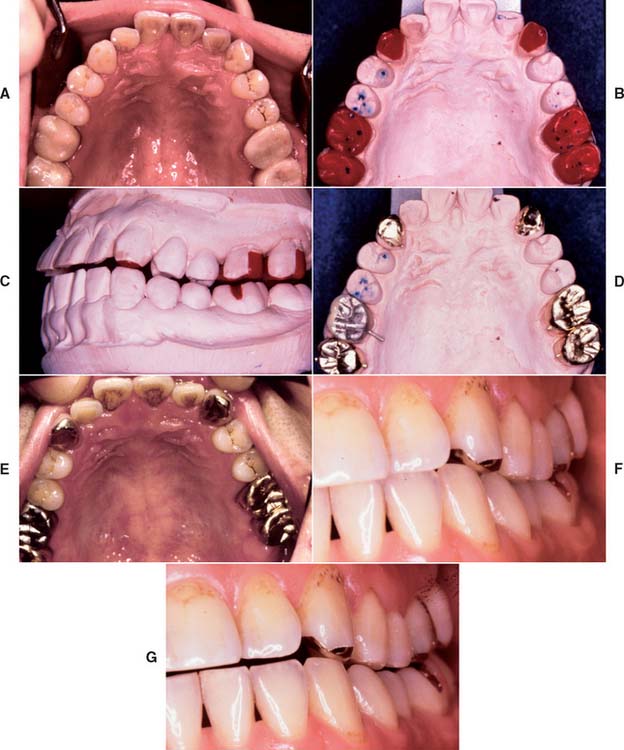

Unfortunately, periodontal disease often occurs after placement of fixed prostheses,26 especially where the cavosurface margin has been placed subgingivally27-29 or the prosthesis is overcontoured.30 Inflammation is more severe with poorly fitting restorations31 (Fig. 32-12), but even “perfect” margins have been associated with periodontitis.32 At recall appointments, particular attention is given to sulcular hemorrhage, furcation involvement, and calculus formation as early signs of periodontal disease. Improperly contoured restorations should be recontoured or replaced.

Fig. 32-12 Periodontal failure resulting from defective fixed prostheses. A, Inadequate margins and contour. B, Appearance before surgery. C, Flap reflected. D, Appearance after surgical recontouring. E, Radiograph of new cast restorations. F, Replacement restorations.

(Courtesy of Dr. C. L. Politis.)